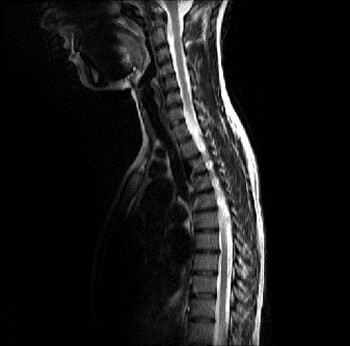

Here we are looking at a variety of different ways to show T2 weighted contrast. In the first image, we have an Axial (which tells us which plane we have acquired the data) T2(which tells us which tissue contrast we have acquired), and the acronym FSE (which tells us that it is a Fast Spin Echo). The second image is also an Axial, and it is T2 weighted, however, it is a diffusion scan which is producing an image that takes into account how well the brain tissue is diffused with blood. As you can see they look quite different and are showing us very different information.

Here we have a Coronal view of the knee, a sagittal view of the shoulder, and an axial view of the foot. All are Fast Spin Echo’s as we see the FSE indication. As you can also see, T1 weighted contrast has a very different appearance compared to T2 weighted contrast on an MRI image.